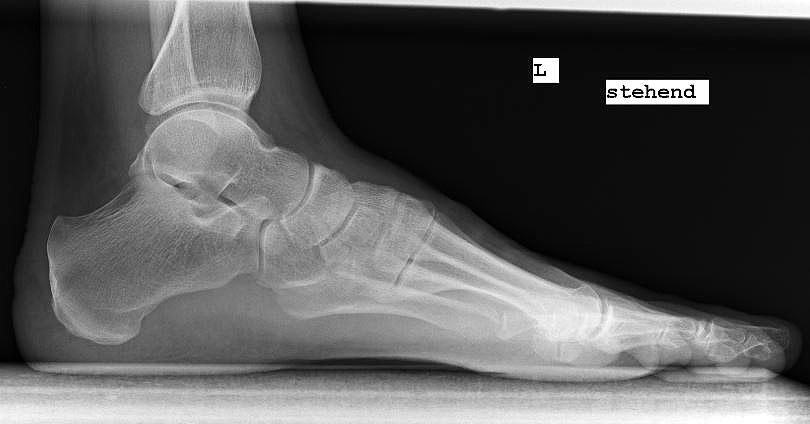

Röntgenaufnahme des Fußes im Stehen im dorsoplantaren und seitlichen Strahlengang (Abb. 1a-b).

Beurteilung des ersten Intermetatarsalwinkels (IMA), des Hallux valgus Winkels (HVA), des distalen (Distal Metatarsal Articular Angle, DMAA) und proximalen Gelenkflächenwinkels der Grundphalanx (Proximal Phalangeal Articular Angle, PPAA).

Abbildung 1a

Abbildung 1b